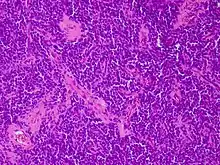

Micrograph of an H&E stained section of a peripheral PNET.

It gets its name because the majority of the cells in the tumor are derived from neuroectoderm, but have not developed and differentiated in the way a normal neuron would, and so the cells appear "primitive". PNET belongs to the Ewing family of tumors.